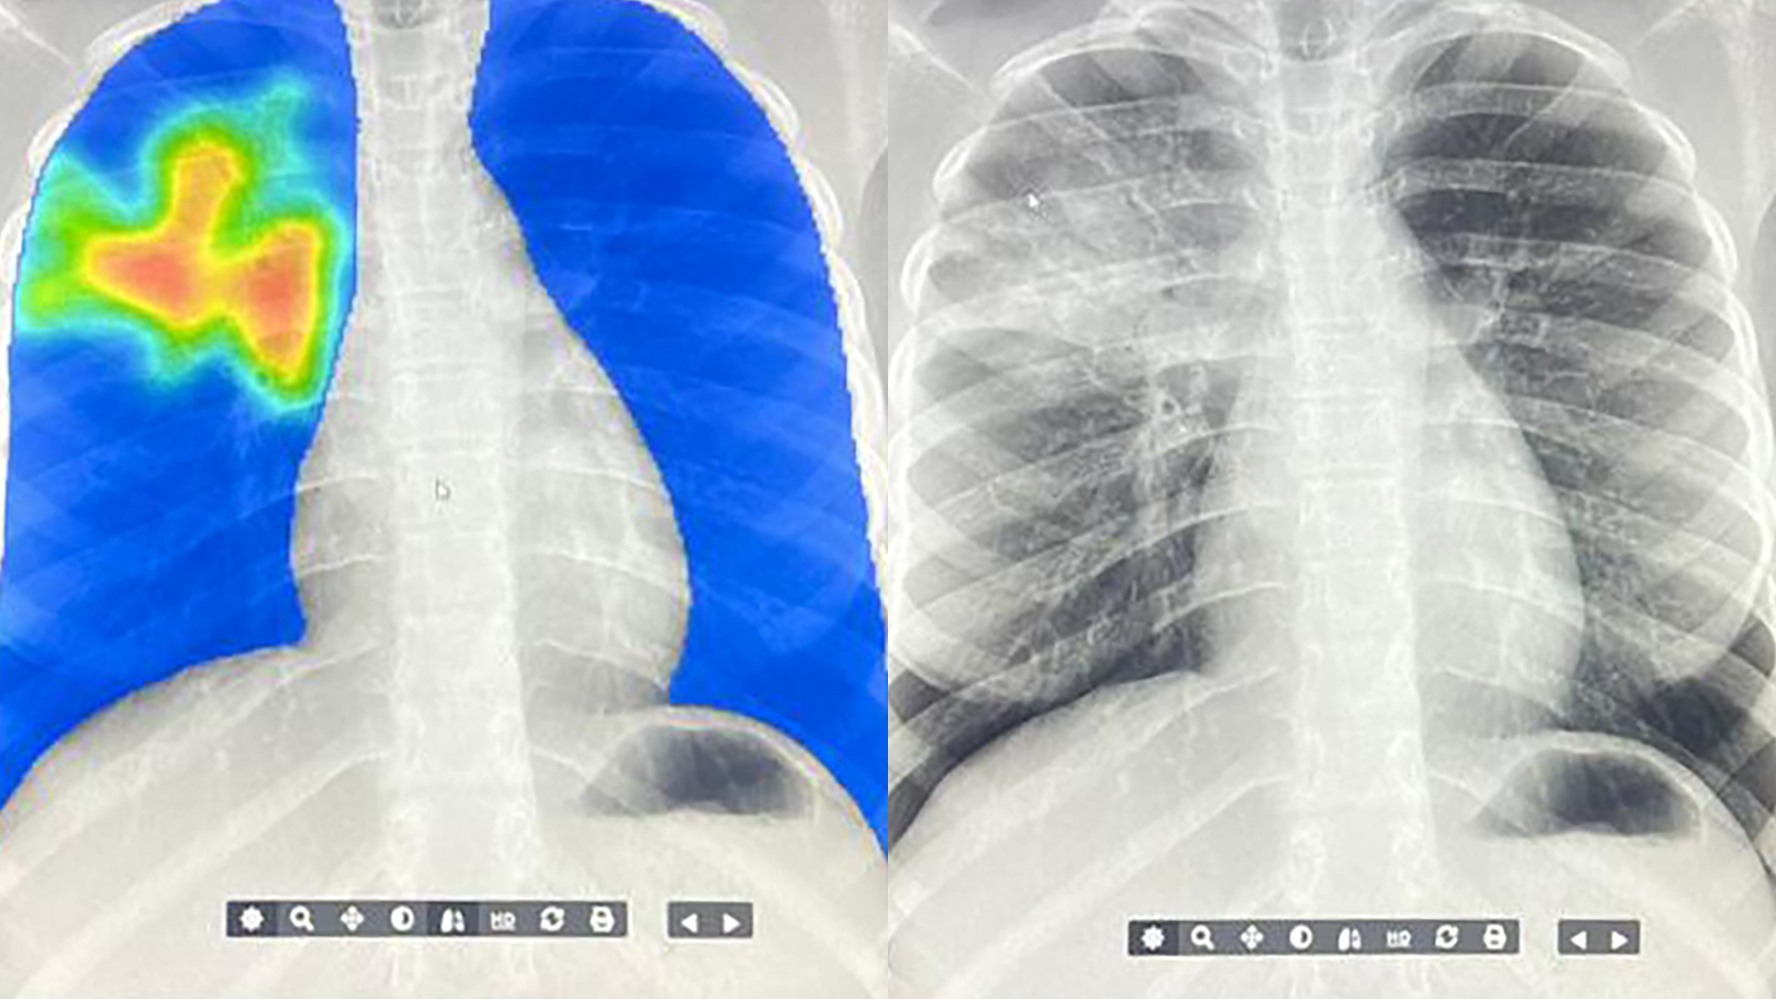

(Image credit: ARCAD Santé PLUS)